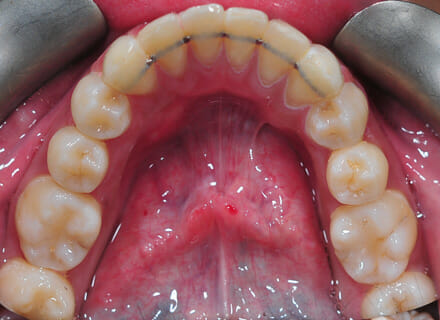

This lady came to us because she said she was goofy – her front teeth were sticking out. In the lower jaw, the teeth didn’t have enough room so 2 teeth had been pushed out of the bite altogether. We fitted a clear brace and were able to reduce the overbite by 80%. We also managed to pull the lower premolars back into the arch. This lady did not require any extractions. She was so pleased with the results especially as no healthy teeth were removed!